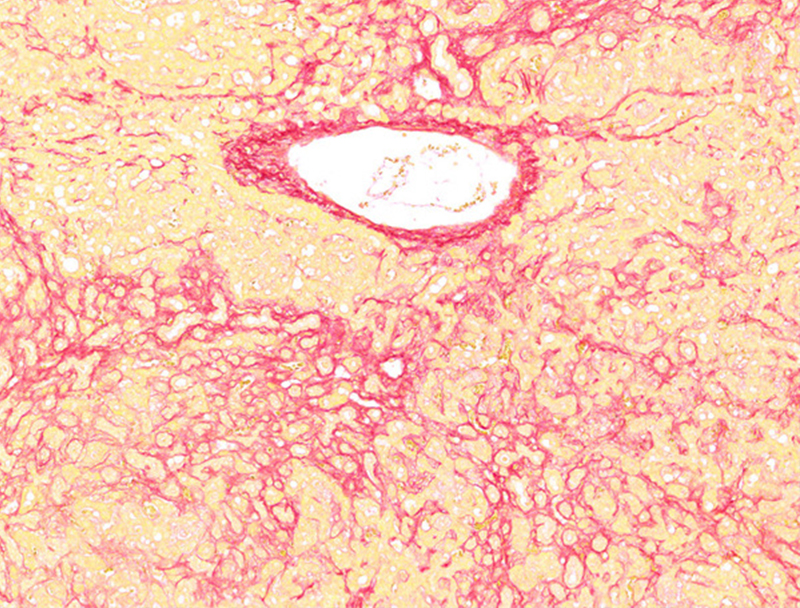

天狼猩红染色

油红O染色